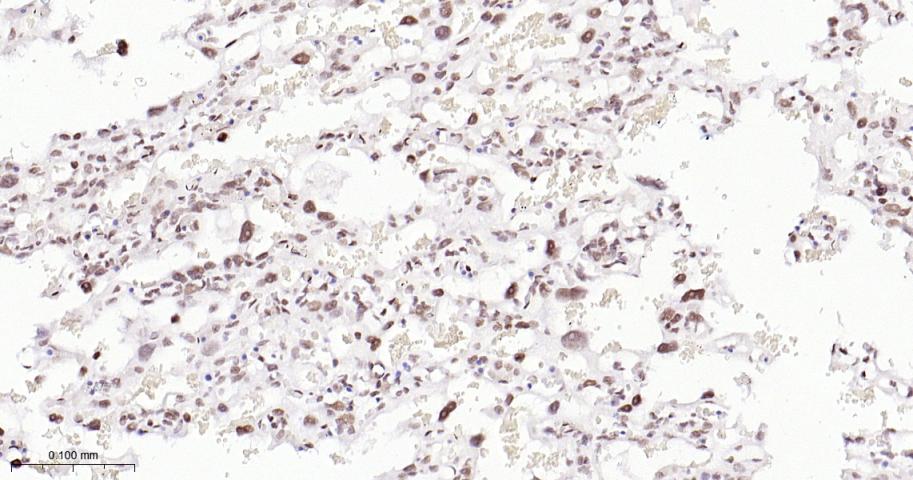

Paraformaldehyde-fixed, paraffin embedded Human Breast Cancer; Antigen retrieval by boiling in sodium citrate buffer (pH6.0) for 15 min; The section was incubated with EHMT2 Monoclonal Antibody, Unconjugated (bsm-61806R) at 1:200 overnight at 4°C, followed by conjugation to the bs-0295G-HRP and DAB (C-0010) staining.